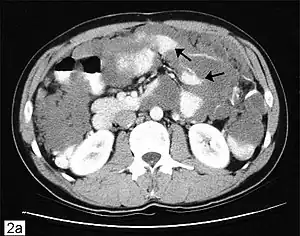

Os exames de diagnóstico podem incluir tomografias, exame de amostras de tecido obtidas por laparoscopia e avaliação de marcadores tumorais. Na maioria dos casos, uma colonoscopia é inadequada como uma ferramenta de diagnóstico porque na maioria dos casos câncer de apêndice invade a cavidade abdominal, mas não o cólon. PET scan pode ser usado para avaliar adenocarcinoma mucinoso de alto grau, mas este teste não é confiável para a detecção de tumores de baixo grau, porque não se tingem bem com o corante usado nas varreduras. Tumores avançados podem ser palpáveis ou descobertos incidentalmente em cirurgias abdominais.